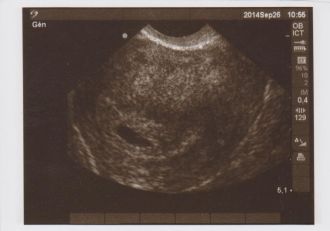

1er RDV chez la gynéco programmé le 26 septembre....

Comme je l'imaginai, c'était un peu tôt mais on a déjà pu voir la poche..., grossesse confirmée donc et bien placée, ouf!!!

Un second RDV a été pris pour vérification de l'évolution le 7 octobre....

Message déposé le 16.11.2014 à 10:45 - Commentaires (1)